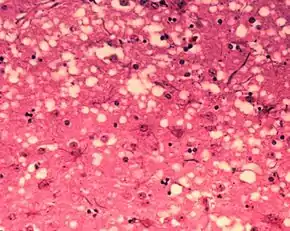

Diagnosis of BSE continues to be a practical problem. It has an incubation period of months to years, during which no signs are noticed, though the pathway of converting the normal brain prion protein (PrP) into the toxic, disease-related PrPSc form has started. At present, no way is known to detect PrPSc reliably except by examining post mortem brain tissue using neuropathological and immunohistochemical methods. Accumulation of the abnormally folded PrPSc form of PrP is a characteristic of the disease, but it is present at very low levels in easily accessible body fluids such as blood or urine. Researchers have tried to develop methods to measure PrPSc, but no methods for use in materials such as blood have been accepted fully.

The traditional method of diagnosis relies on histopathological examination of the medulla oblongata of the brain, and other tissues, post mortem. Immunohistochemistry can be used to demonstrate prion protein accumulation.[25]